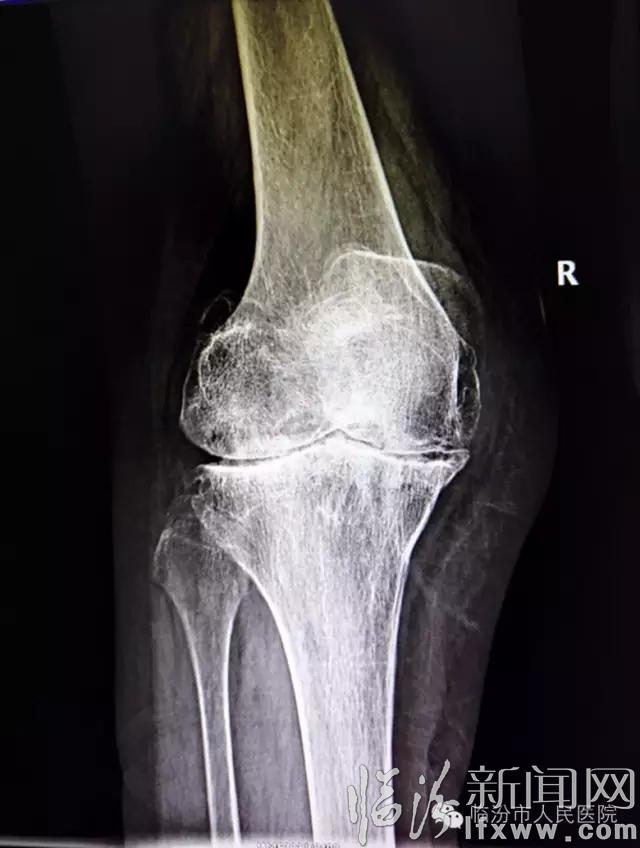

临汾新闻网讯 近日,临汾市人民医院骨科主任刘建团队完成膝关节强直畸形人工全膝关节置换术。

膝关节强直多由膝关节创伤、手术、感染等原因所引起,膝关节强直性畸形使患者的生活质量严重下降,随着人工全膝关节置换技术的提高,此手术已应用于这一领域。

膝关节强直畸形患者行人工全膝关节置换术难度较大,技术要求很高,需要有丰富经验的医生才能够完成。以往强直膝患者均需到上级医院进行手术,随着市医院骨科技术的提高,目前已可独立完成膝关节强直的膝关节表面置换手术。且术后患者均恢复良好,得到了满意的效果,大大方便了患者的诊治过程,同时表明市医院关节外科技术在省内已处于先进水平。(市医院骨科)